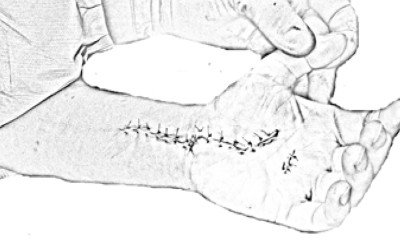

Dupuytren's disease is a disease that affects the palmar fascia, an anatomical structure found in the palm of the hand, between the skin and the tendons and that connects the skin to the deep planes, being responsible for the fact that the palmar skin is (...)

Dupuytren's disease